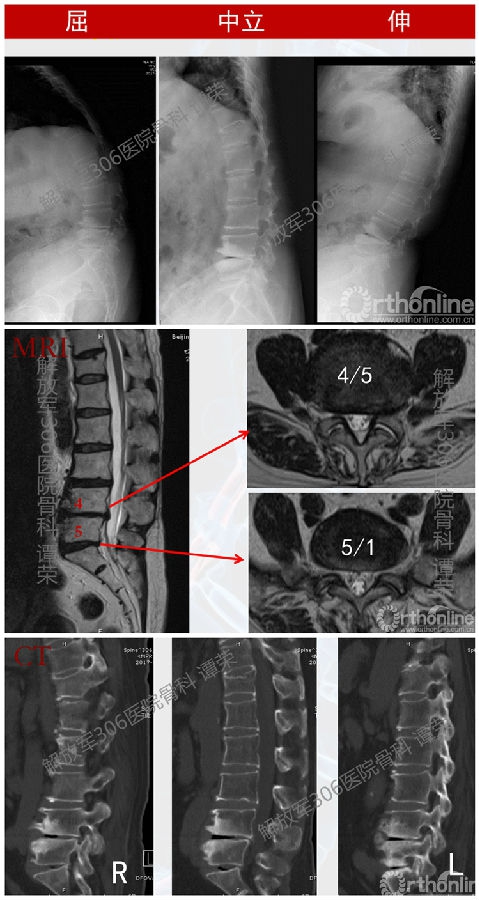

患者女,64岁。腰痛15年加重6个月。步行或站立超过5分钟即出现腰痛,卧床休息可以明显缓解,下午症状重于上午,偶有右下肢放射痛。体查:胸腰椎后凸畸形,无神经系统异常。腰痛VAS评分:行走-7,休息-3。

影像学检查

诊断

1、退变性胸腰椎后凸?

2、腰椎管狭窄症?

3、其它?

经考虑最终采用(T6-S2)SOP。术后患者身高增高5cm。